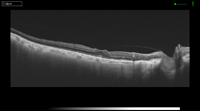

Figura 8. Pseudoagujero con membrana epiretiniana.

Figura 9. Membrana epiretiniana con engrosamiento macular.

Figura 10. Membrana epiretiniana con tracción foveolar, perdiendo su perfil natural.